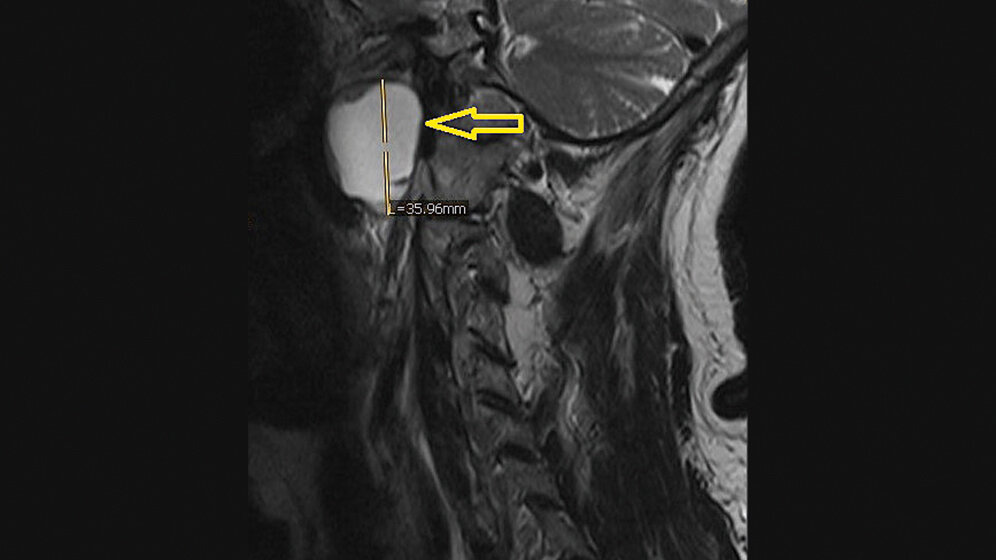

Die Halszysten sind kongenitale Anomalien, verursacht durch Überbleibsel der Kiemenbogengänge. Sie stellen etwa 30 % aller Anomalien des Halsbereiches dar. Viele der Halszysten sind asymptomatisch. Ultraschall, Computertomografie und Kernspintomografie werden zum Nachweis eingesetzt und, um im Falle einer Infektion oder Größenwachstum, die chirurgische Behandlung zu planen.

Branchial cleft cyst is a congenital anomaly, caused by persistent elements of branchial apparatus. It constitutes 30 % of all congenital anomalies of the neck. Most of them are asymptomatic. Ultrasonography, computerized tomography and magnetic resonance may be used to evaluate and to plan the surgical treatment in case of infection or growing up.